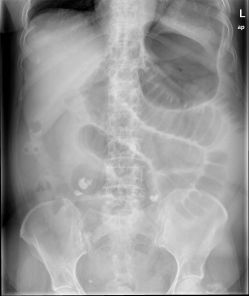

La escasa rentabilidad diagnóstica de la radiografía de abdomen en patología urgente contrasta con el elevado número de exploraciones que se realizan.